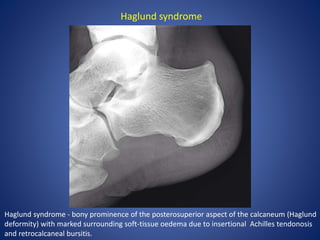

Haglund syndrome - bony prominence of the posterosuperior aspect of the calcaneum (Haglund

deformity) with marked surrounding soft-tissue oedema due to insertional Achilles tendonosis

and retrocalcaneal bursitis.

Haglund syndrome

Haglund syndrome -bony prominence of the posterosuperior aspect of the calcaneum (Haglund deformity) with marked surrounding soft-tissue oedema due to insertional Achilles tendonosis and retrocalcaneal bursitis. Haglund syndrome